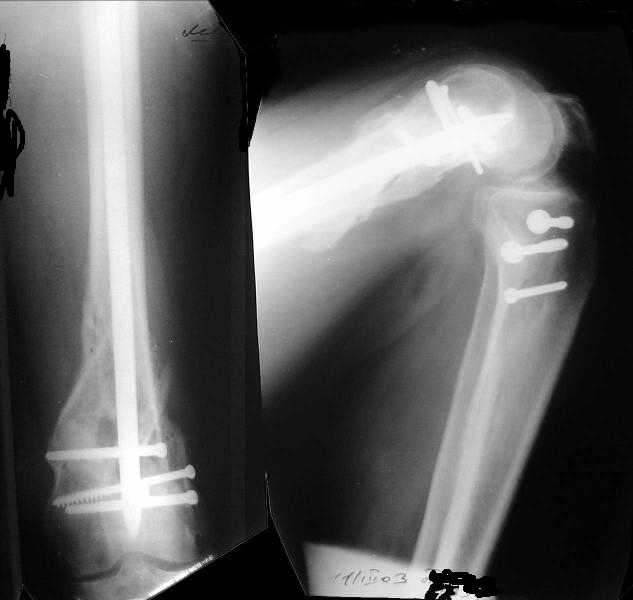

Мужчина 52 лет оперирован у нас 1,5 года назад по поводу перелома проксимального отдела большеберцовой кости. Все было неплохо, сгибал колено градусов до 60, ходил с полной нагрузкой, давно уже работал (служащий). Пару дней назад упал на скользкой улице - снимок в приложении. Какие предложения по лечению (пока первая мысль опять про закрытый интрамедуллярный остеосинтез)? И более широкий вопрос - как быть с локальным остеопорозом от бездействия после травм?

Merry Xmas!!! A male 52 years old was treated 1,5 years ago in our unit - ORIF of the proximal tibia. In 1 year follow-up all was OK - flexion 130, full WB, returned to work (white collar). Two days ago he fell on a slippery sidewalk - x-rays attached. How would you manage the injury? My first thought is closed nailing. And more common question - what we should do routinely with posttraumatic local osteoporosis? When full WB and function of the extremity is restored how long does a problem of such fractures exist?